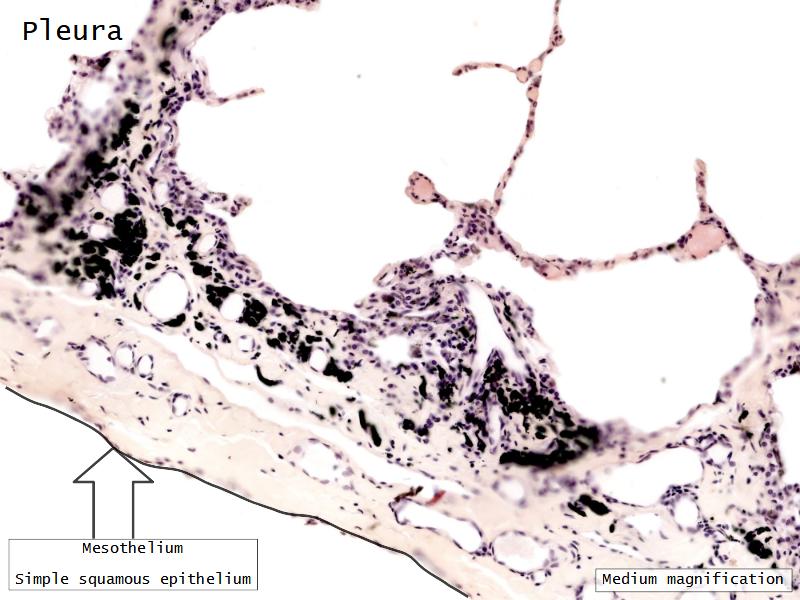

Barriers

- Skin

- Blood-air